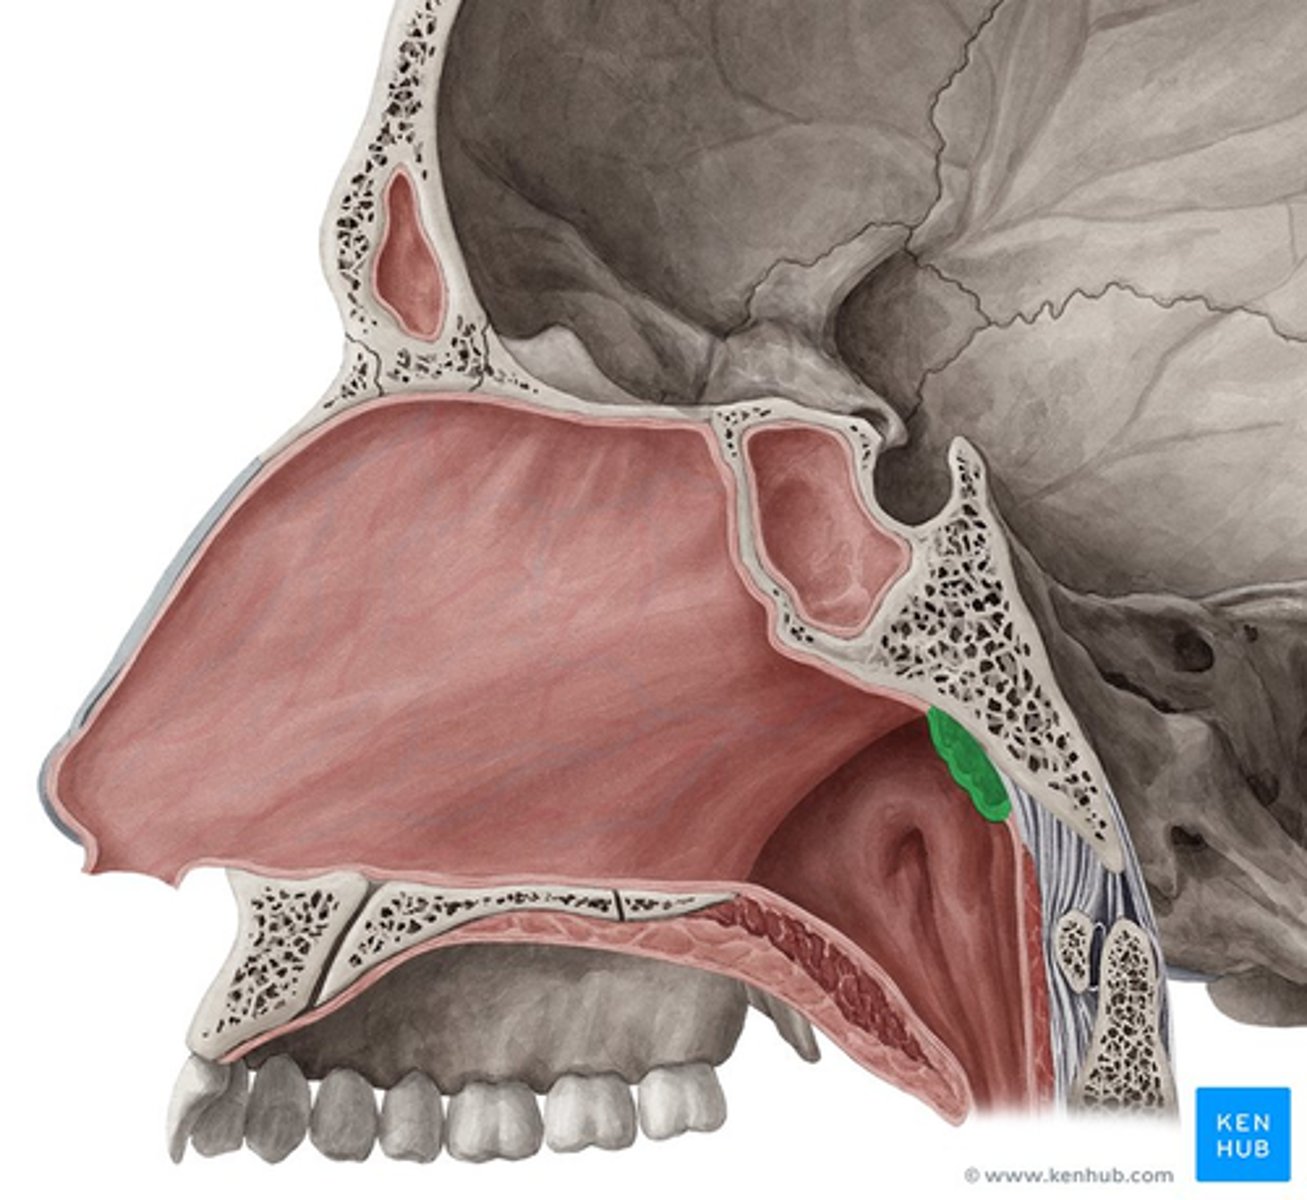

sphenoidal sinus

pharyngeal tonsil

tonus tubaris

opening of pharyngotympanic tube

salpingopharyngeal fold

superior meatus

middle meatus

inferior meatus

inferior nasal concha

uvula

frontal sinus

nasal septum